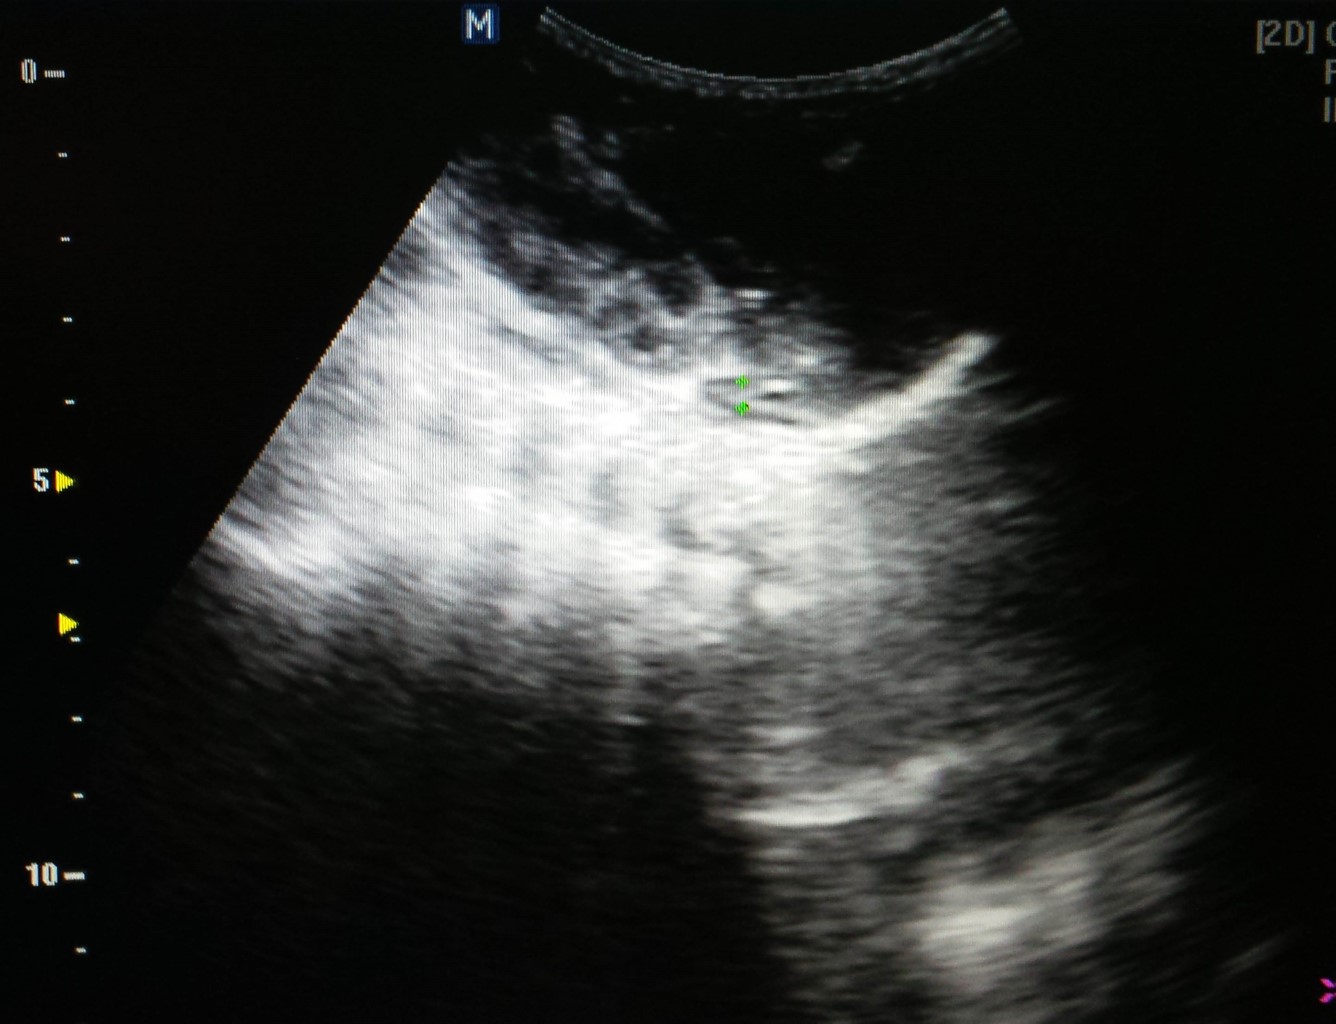

Se detectó anemia (12.5 gramos de hemoglobina) como único dato anormal. El ultrasonido transfontanelar fue normal. Pero en la ecografía abdominal se observó una imagen compleja a nivel suprarrenal derecha, que medía 44 × 31 mm, la cual correspondía a HS del lado derecha (Figura 1).

Figura 1